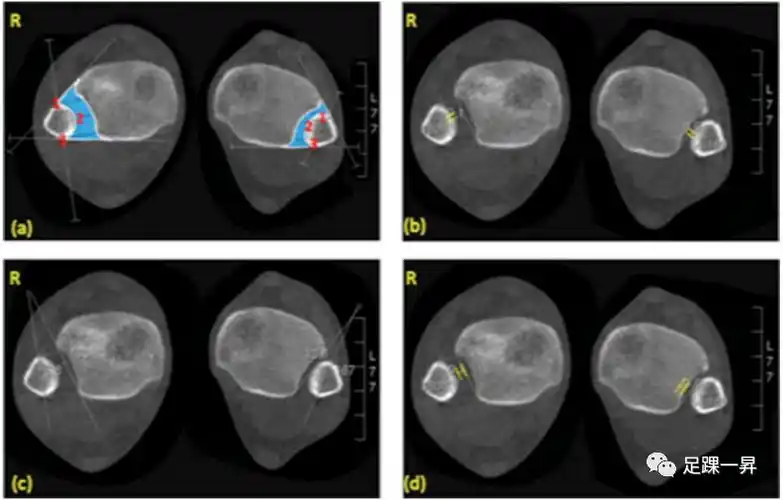

表3为下胫腓联合损伤的ct测量方法.